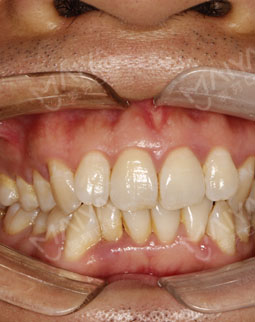

过去的困扰

作为深圳电视台的一名主持人,很多时候需要用更精致的形象面对观众,这也是主持人的自我修养。在近距离的视频拍摄中,因为牙齿不好看的关系,摄像师很少给到我脖子以上的大特写,就算有特写,也不敢咧嘴大笑,因此还错过一些好的工作机会!对我生活的影响就是,吃饭的时候,牙齿还经常卡刺,吃完之后需要花费时间去剔牙和漱口。 其实我很早想矫正,但是当时给的方案是传统的金属牙套,这显然我的职业是不允许的!毕竟,事业为主要阶段的现在,社交也很重要。如今已经年过30岁,我一直在找一种既能快速矫牙又不伤牙的方式。